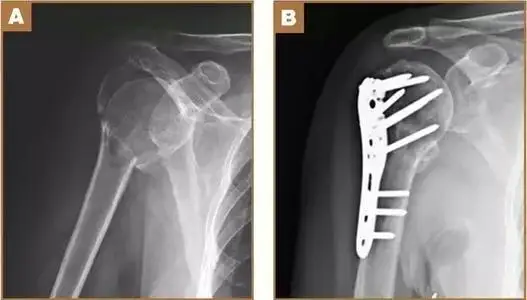

Product Features of VA Variable Angle Distal Lateral Humeral Locking Plate

◆ Design of distal multi-axial locking hole

The maximum angle of the multi-axial locking screw in all directions away from the axis is 15 °, which can better support the joint surface and fix the fracture block, enhance the anti rotation stability by cross fixation of the fracture block, and provide the possibility of re implantation of the screw.

◆ Anatomical Design

Even Complex fractures can be perfectly fitted without shaping.

◆ Stable Angulation

The angular stabilization structure is designed to improve the holding power of osteoporosis patients and multiple fracture cases.

It provides the best stability and helps to prevent reduction loss.

◆ Round Blunt Head Design

Reduce the impact of shoulder seam and prevent postoperative pain.

◆ Locking & Complression Design

To meet the doctor's requirements for different fractures, compression and locking functions can be flexibly selected in one hole.

Fixations at different angles is selected according to different fracture sites to form different angle structures so as to

achieve the stability of later reduction.

◆ Head End

Locking holes are the main part of the head, which are designed from different angles. The screw is allowed to be stably placed in the axial direction, so that the structure is stable and the elongated type can cover a wider range of fractures.

◆ Main Part

Conjugative hole for locking & compression. Free choice of locking screw & compression screw.